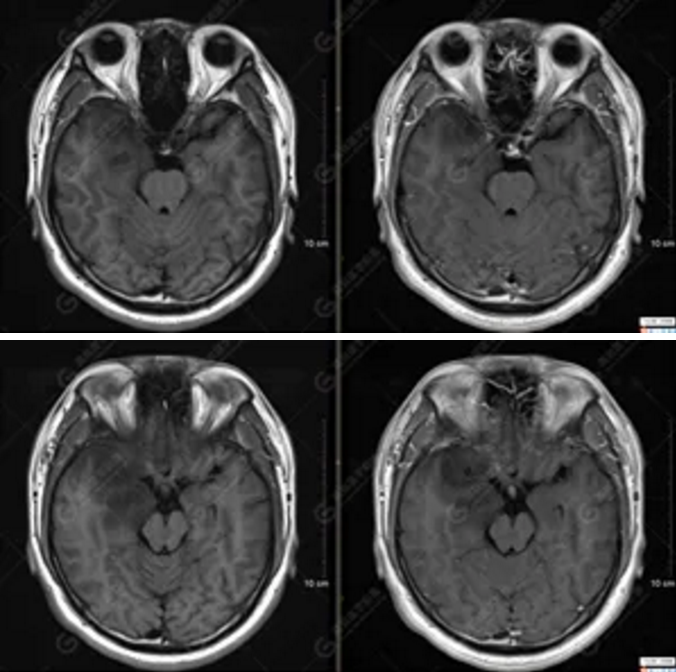

以上為DTI成像,圖1為皮質(zhì)脊髓束,圖2為胼胝體束,圖3為扣帶回束,圖4為額枕束。DTI成像示右側(cè)額枕束前部明顯受壓、部分未見顯示;胼胝體束、雙側(cè)扣帶束、皮質(zhì)脊髓束及左側(cè)額枕束形態(tài)可,纖維束未見明顯破壞,未見明顯稀疏減少。

2.DTI成像示右側(cè)額枕束前部明顯受壓、部分未見顯示。